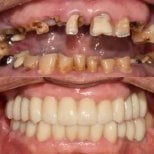

4. Full-mouth dental implants (All-on-4 / All-on-6)

For patients who’ve lost most or all of their natural teeth, Korean clinics offer full-arch restorations. These involve placing 4 or 6 implants to support a fixed arch of prosthetic teeth. It’s a stable, long-term alternative to removable dentures.

- Check reviews and patient photos. Look for real before-and-after cases and feedback from international patients.